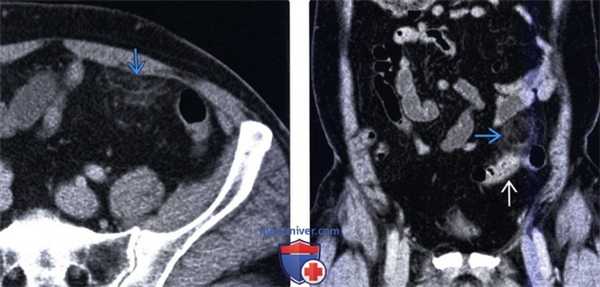

(Слева) На аксиальной КТ с контрастным усилением определяется небольшое, содержащее жир объемное образование с гиперденсным «ободком» и воспалительными изменениями прилежащих тканей в правом нижнем квадранте сальника: «классический» внешний вид и локализация изменений при инфаркте.

(Справа) На корональной КТ с контрастированием у пациента после эндоскопической дистальной панкреатэктомии визуализируется содержащее жир объемное образование в левом верхнем квадранте сальника, представляющее собой массивный инфаркт. Инфаркты сальника после оперативного вмешательства могут быть весьма массивными.

2. КТ при инфаркте сальника:

• Неоднородное инкапсулированное объемное образование в сальнике между передней брюшной стенкой и ободочной кишкой:

о Может иметь различную плотность, но обычно выглядит как очаг жировой плотности (от -20 до -50 ед. Хаунсфилда)

о Края образования обычно четкие, имеется гиперденсный «ободок» по периферии, возникающий, в частности, после оперативного вмешательства:

- Инфаркты на ранних стадиях могут выглядеть расплывчатыми: определяются как плохо отграниченные участки помутнения жировой клетчатки без наличия отдельно лежащего объемного образования

о Не определяется симптом «центрального пятна», как при ап-пендагите

о Патологическая извитость сосудов, питающих сальник, нарушение проходимости которых может привести к инфаркту

• Часто сочетается с воспалительными изменениями окружающих тканей и помутнением жировой клетчатки ± с наличием малого количества жидкости

(Слева) На корональной КТ с контрастным усилением у пациента с болевой симптоматикой определяется инкапсулированное, содержащее жир объемное образование в правом нижнем квадранте сальника с помутнением окружающей жировой клетчатки, что характерно для инфаркта.

(Справа) На аксиальной КТ с контрастом у пациента после экстренной дистальной панкреатэктомии выявлено большое объемное образование с четкими контурами в левом верхнем квадранте сальника. Обратите внимание на наличие включений с плотностью жира в структуре образования. Инфаркты сальника, как в этом случае, могут иметь весьма большие размеры и симулировать опухоль (липосаркома) или канцероматоз.